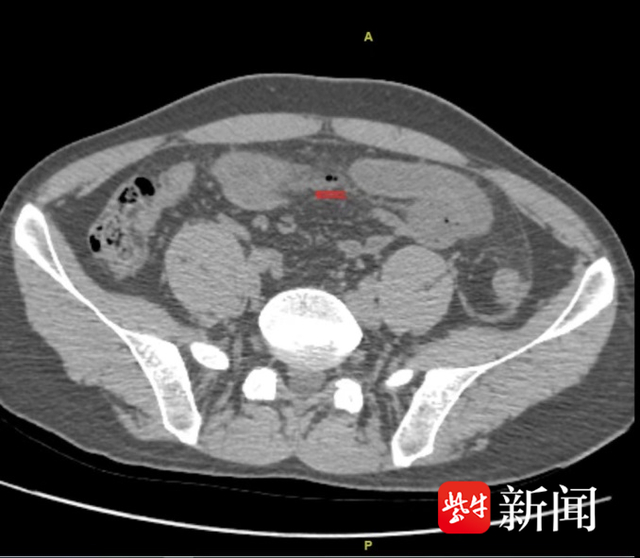

第三天一早,症状持续加重的小张赶紧来到南京医科大学附属明基医院急诊就诊。急诊医生询问病史时,小张表示腹痛不到1天,原因也不清楚。在急诊就完善了腹部检查,CT提示有游离气体,这是消化道穿孔的表现,便立即联系普外科医生(普外科是急腹症的首要会诊科室)。

普外科主任医师王长林仔细阅片发现患者肠管内见高密度影,尖锐细长,像是鱼刺,再次追问小张有没有吃鱼?小张这才恍然大悟,自己两天前确实与好友聚餐吃过鱼,但是吃饭过程中自己并没有感觉卡到鱼刺,吃完后也没觉得不舒服。为什么会是鱼刺惹的祸?

“小肠的长度一般在4米到6米左右,在腹腔内弯曲堆叠在一起,鱼刺很难确定在小肠的哪一段,而且鱼刺细小,2天过去了,它很可能会游离到其他地方,需要在手术过程中仔细查找。”王长林主任说,穿孔位置不是一个孔,是一片小肠漏气,修补存在肠瘘风险。果不其然,经过仔细探找,在距离穿孔位置大概20cm的地方找到了鱼刺,在安全的情况下,将鱼刺送回到穿孔的位置,成功取出,并完成小肠的部分切除吻合手术,避免急性期修补导致的肠瘘。